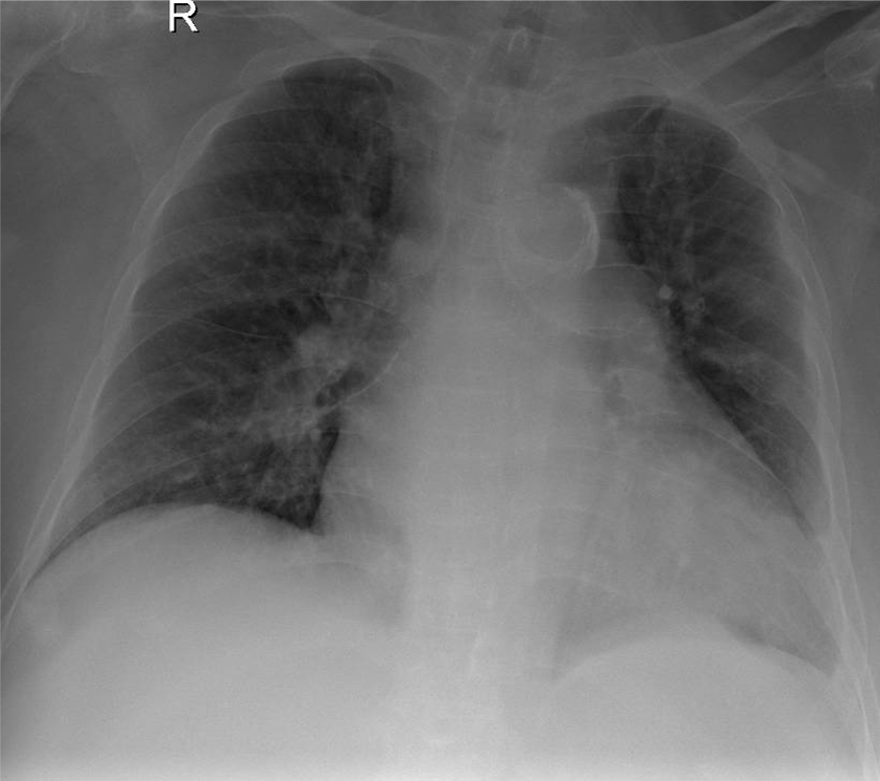

Hãy phân tích tình huống Nữ 54 tuổi -CĐ:Tràn dịch màng phổi (P) lượng nhiều nghi do lao

1-Khí quản lệch (T) 2-Tràn dịch màng phổi (P) lượng nhiều 3-Bóng tim và trung thất lệch (T)